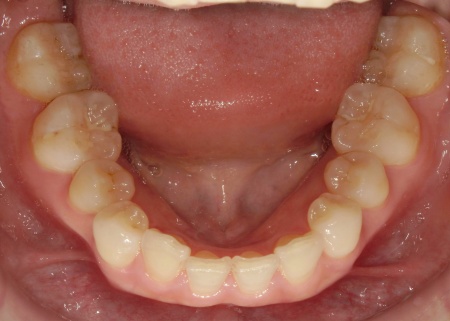

拝見したところ、叢生(そうせい)が上下前歯に確認できました。

叢生とは歯が並ぶスペースが足りないために、歯が重なったりねじれたりして生えてしまう状態のことです。

今回のケースでは上前歯にやや目立つ重なりがあり、下前歯は軽度の叢生が見られました。

下あごの叢生は比較的軽度であり奥歯の噛み合わせにも問題がなかったこと、また上あごのみの治療にすることで費用面の負担も抑えられることから、今回は上あごのみの矯正治療を行う方針としています。